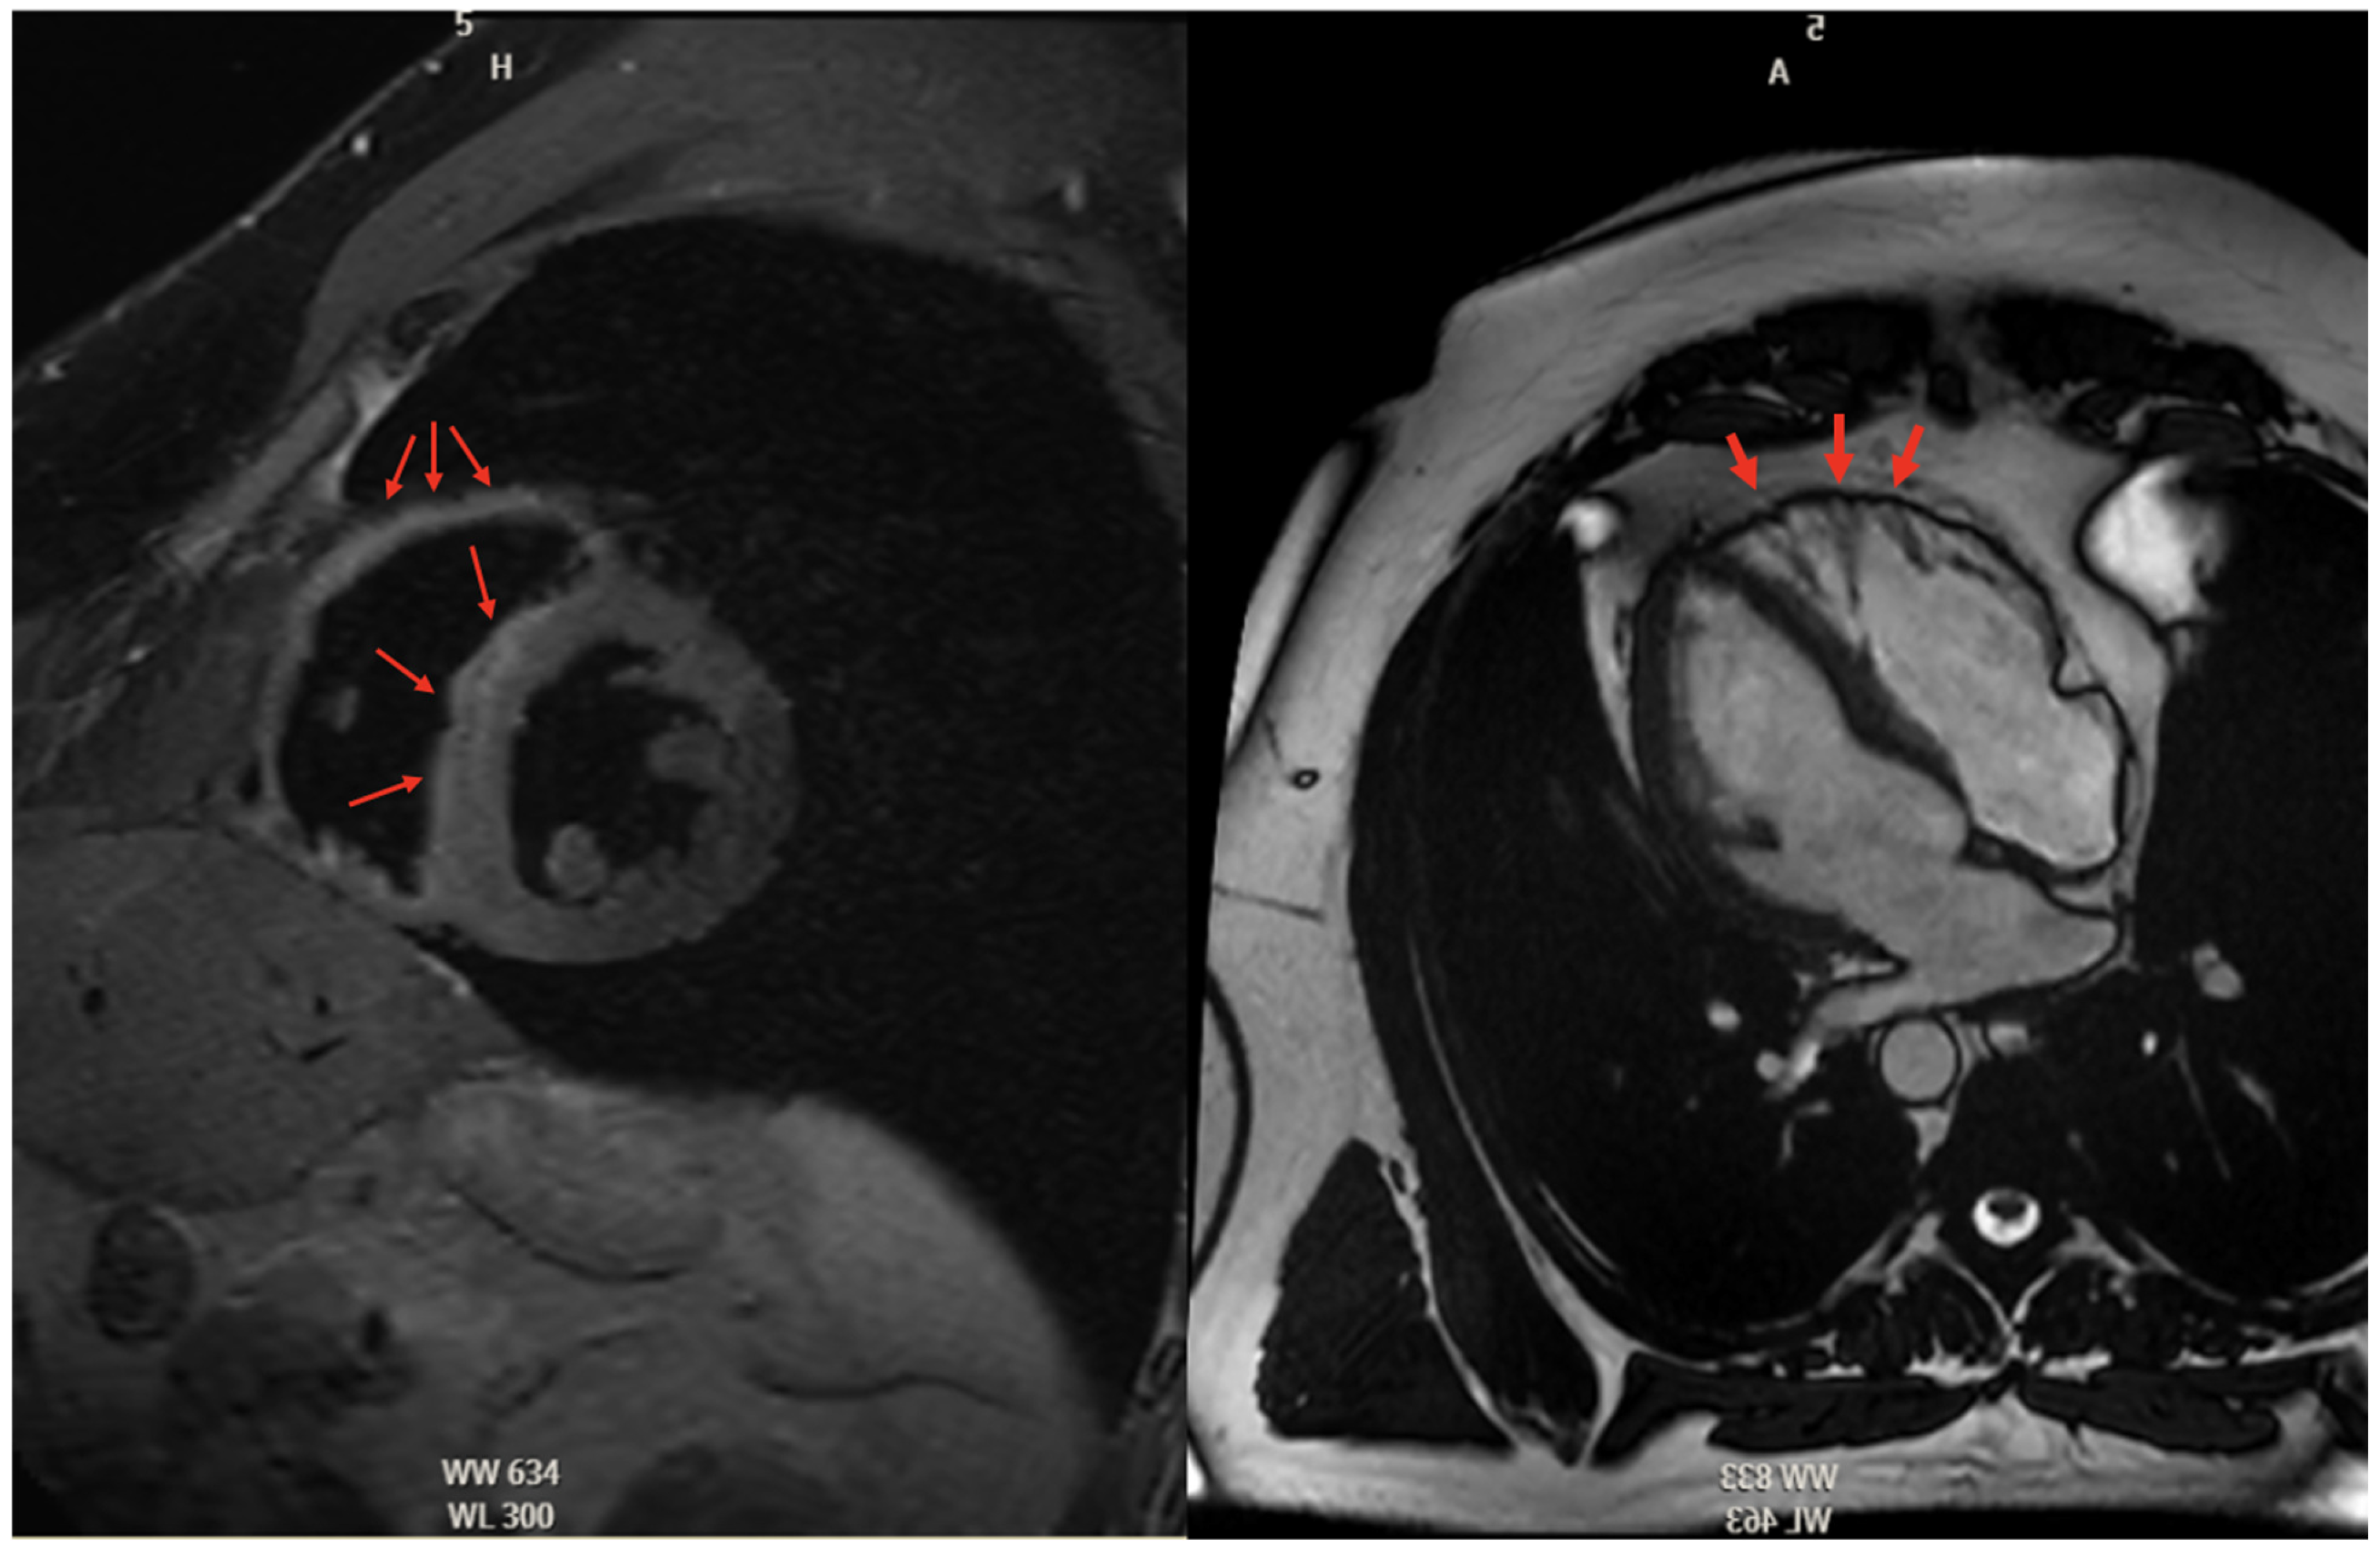

5.2.3. Cardiac Magnetic Resonance High Risk